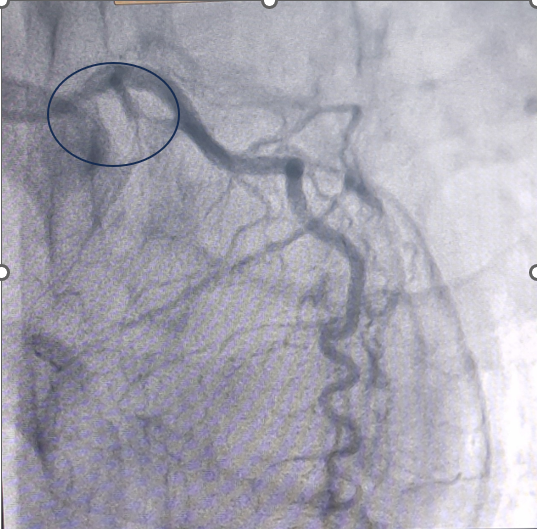

Người bệnh được chỉ định chụp động mạch vành qua hệ thống máy chụp mạch máu số hoá xoá nền (DSA), kết quả cho thấy tắc hoàn toàn cả 3 nhánh động mạch vành, đặc biệt các mạch tắc được nuôi dưỡng bằng mạch tuần hoàn bàng hệ từ chính những nhánh tắc.

Đây là trường hợp tổn thương mạch vành nặng, phức tạp và khá hiếm gặp. Người bệnh có tổn thương động mạch vành tiến triển từ từ và kéo dài từ trước, các mạch máu tuần hoàn phụ phát triển nhanh đủ để ngăn cản sự thiếu máu cơ tim nên trước đó người bệnh không có dấu hiệu bất thường. Bệnh chỉ được phát hiện khi các mạch máu phụ phát triển không đủ lớn để duy trì lưu lượng máu đáp ứng nhu cầu oxy của cơ tim gây thiếu máu mạch vành, gây nhồi máu cơ tim cấp.

| Tắc hoàn toàn động mạch liên thất trước bên trái Mạch tuần hoàn bàng hệ từ động mạch vành phải sang nuôi động mạch vành trái |